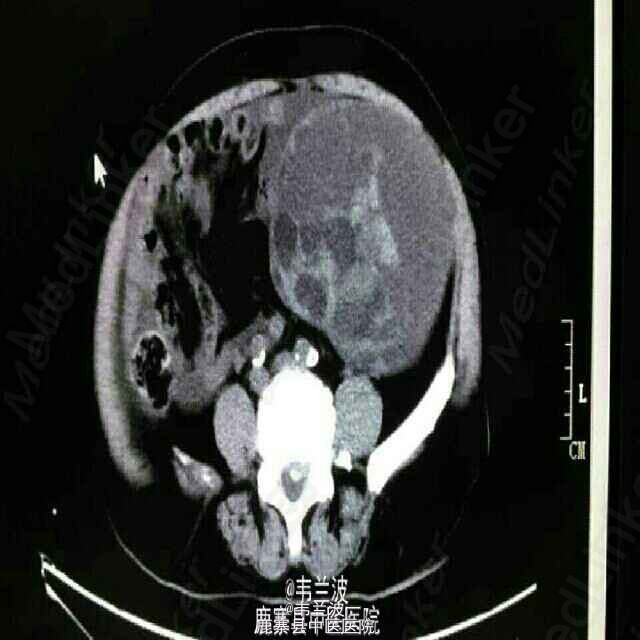

腹部肿块

中老年妇女,发现腹部包块半年。其他病史不详,未作增强。大家讨论一下什么疾病可能性大。